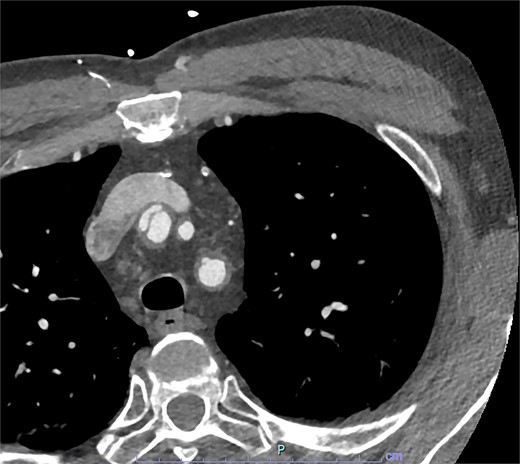

On arrive to the emergency department, the patient was found to be hypertensive with a blood pressure of 220/120 mmHg. Physical examination of the patient revealed no significant clinical findings. Serial troponins with corresponding ECG’s were undertaken which demonstrated no new evidence of myocardial ischaemia. Based upon the patient’s symptomatology, he underwent a CT aortogram which demonstrated a dissection arising from the proximal brachiocephalic artery. No dissection was noted in the ascending aorta, and there was no evidence of the brachiocephalic artery dissection extending into the subclavian or carotid arteries (Figs 1–3).

Axial slice from CT aortogram demonstrating the proximal aspect of the dissection flap.